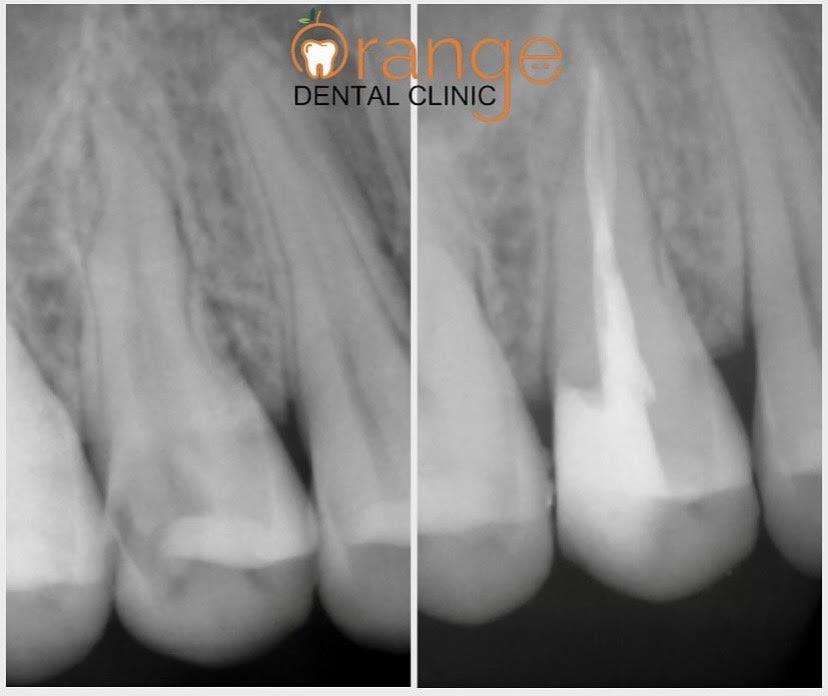

RADIOGRAPHIC CASE PRESENTATION

Root Canal Treatment Treatment